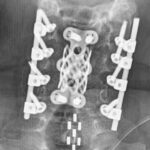

Estimulación Eléctrica Epidural (EES)

La estimulación eléctrica epidural (EES) es una herramienta poderosa para potenciar la neuroplasticidad. Este tratamiento suministra corrientes eléctricas directas a la médula espinal, alterando significativamente su función con el tiempo. Los pacientes que utilizan EES durante períodos prolongados suelen mostrar mejoras medibles en la función de la médula espinal y en la neuroplasticidad.